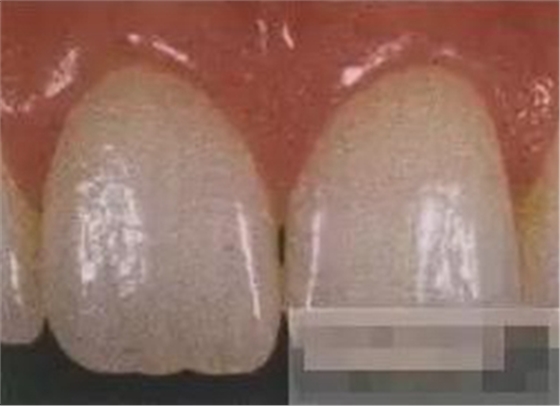

【分層堆塑】

A4本質(zhì)堆塑

Dr.Vanini建議如果牙醫(yī)選色有疑惑的話,最好應(yīng)用顏色深一些的牙本質(zhì)樹脂。

A3本質(zhì)堆塑

發(fā)育葉制作

白堊斑

切端琥珀色制作

A3頸部堆塑

涂布防氧化劑

充填初步完成